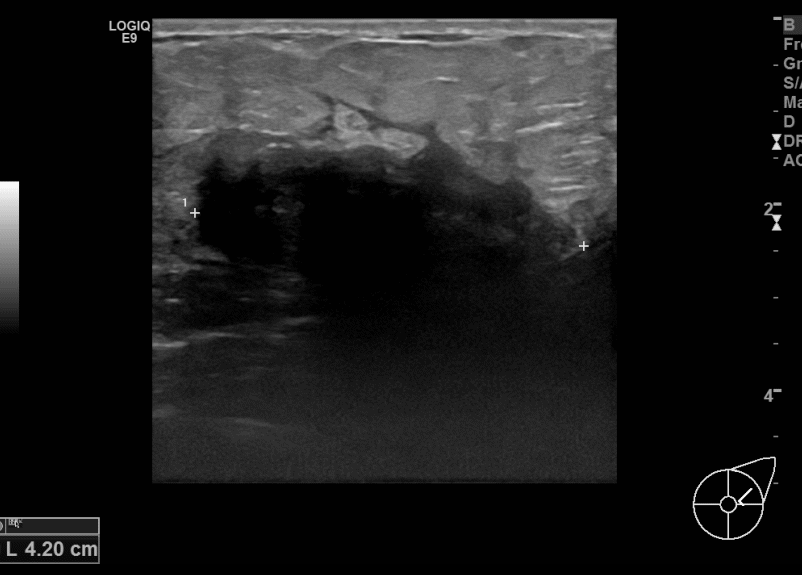

아산유외과개원후 688번째 유방암진단

상기환자 만져진멍울있어 내원하신 60대여성분으로 좌측유방

의심스러운 혹 조직검사시행후 유방암 진단되었습니다